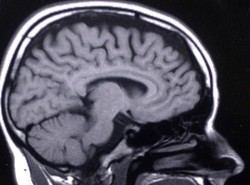

Z pomocą funkcjonalnego rezonansu magnetycznego, tomografu komputerowego oraz specjalnego programu komputerowego Brainvox naukowcy stworzyli trójwymiarowe, szczegółowe mapy mózgu ochotników, a zwłaszcza interesującego ich rejonu kory przedczołowej (tzw. VPMC). Badany fragment jest połączony z korą czołową odpowiedzialną za złożone operacje umysłowe, m.in. poczucie moralności, oraz z pniem mózgu, strukturą sterującą fizjologiczną reakcją organizmu na bodźce emocjonalne.